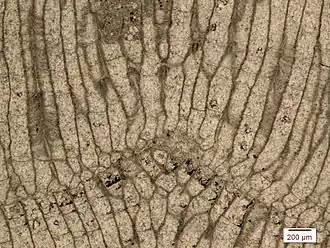

For light microscopy, a knife mounted in a microtome is used to cut tissue sections (typically between 5-15 micrometers thick) which are mounted on a glass microscope slide.[9] For transmission electron microscopy (TEM), a diamond or glass knife mounted in an ultramicrotome is used to cut between 50 and 150 nanometer thick tissue sections.[9]

Historadiography

In historadiography, a slide (sometimes stained histochemically) is X-rayed. More commonly, autoradiography is used in visualizing the locations to which a radioactive substance has been transported within the body, such as cells in S phase (undergoing DNA replication) which incorporate tritiated thymidine, or sites to which radiolabeled nucleic acid probes bind in in situ hybridization. For autoradiography on a microscopic level, the slide is typically dipped into liquid nuclear tract emulsion, which dries to form the exposure film. Individual silver grains in the film are visualized with dark field microscopy.